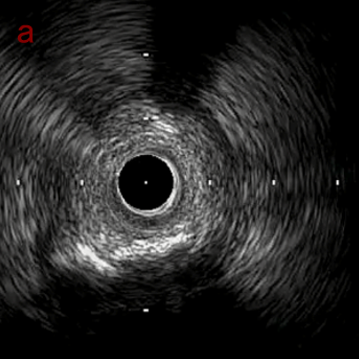

IVUS imaging

IVUSでは8時方向からPD枝がはいいてくる。

PreのIVUSではaの部位のみlipid plaqueを認め削ることでdistal embolismのリスクがあり、そのほかは270度の偏心性石灰化であるがwire biasは良好。

OAS low speedによる引きを赤線の区間行う方針とした。